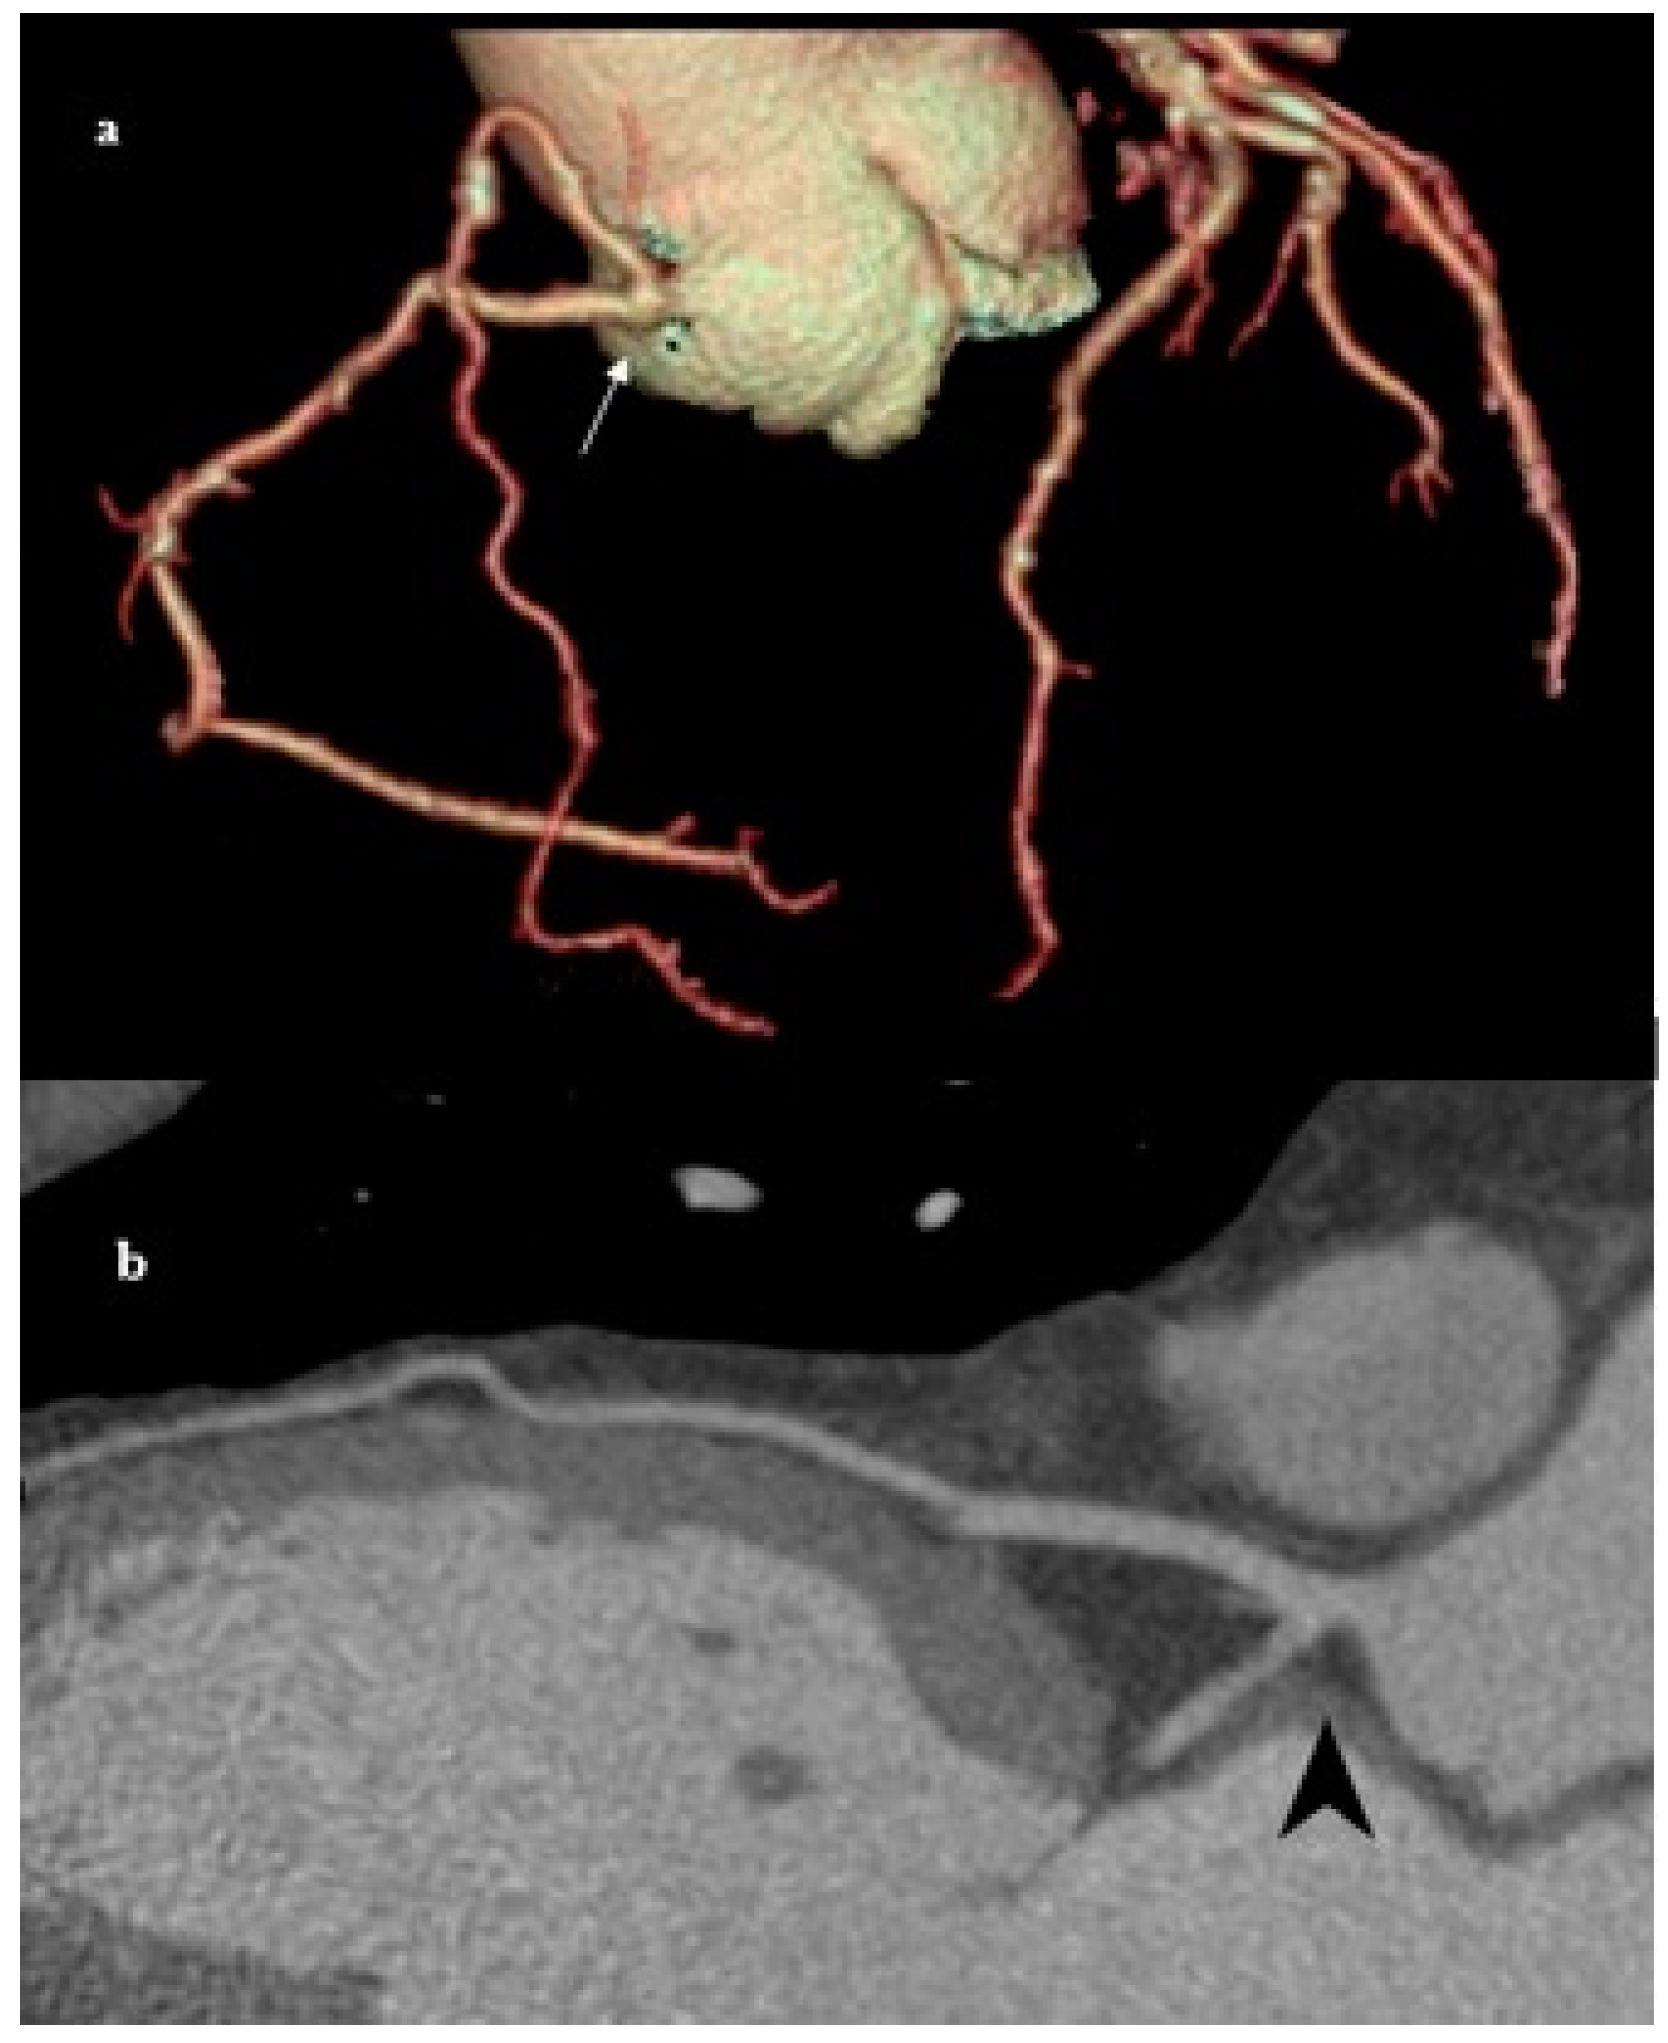

The LMA originates in the left sinus of Valsalva. It soon branches into the LAD and LCX, which supply the left ventricular wall and most of the interventricular septum (Figure 1). This specific coronary variation occurs when the LMA is congenitally absent. Consequently, the LAD and LCX originate separately from the left sinus of Valsalva [16]. It is rare and remains asymptomatic in most cases [17]. Some patients present with chest pain upon exertion, palpitations, and syncope. Angina and arrhythmia manifestations should be assessed cautiously, and the vigilant monitoring of symptoms is necessary to respond to escalation promptly. During catheterization, angiography of the CA, LAD, and LCX arising separately from the left sinus of Valsalva can be easily misdiagnosed as a coronary occlusion or atresia if the operator evaluates only one orifice at a time. MDCT can accurately provide crucial diagnostic information about the origin, course, and anatomical relationships of the coronary arteries and thus accurately detect congenital anomalies of the coronary vessels [18].

Figure 1. MDCT images presenting an absent LMA. (a) Volume-rendered (VR) MDCT images show an absent LMA with separate origins of LCX and LAD from the left sinus of Valsalva. (b) Planar view of LAD and LCX with its own separate origin from the left sinus (black arrow). This variant, although often asymptomatic, is important to recognize preoperatively or prior to coronary interventions to avoid complications during catheterization or surgery.